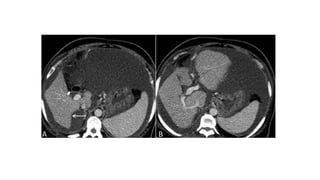

• #21 Axial and coronal contrast-enhanced Ct (A,B) a small liver with smooth margins and massive splenomegaly. Note the infarcts in the upper pole of spleen . But there is no ascites. (C,D) Hypodense filling defects and calcifications in the portal vein due to portal vein thrombosis.